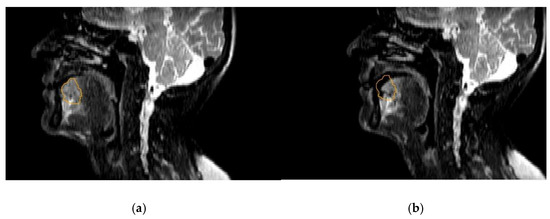

- Ligtenberg, H.; Schakel, T.; Dankbaar, J.W.; Ruiter, L.N.; Peltenburg, B.; Willems, S.M.; Kasperts, N.; Terhaard, C.H.J.; Raaijmakers, C.P.J.; Philippens, M.E.P. Target Volume Delineation Using Diffusion-weighted Imaging for MR-guided Radiotherapy: A Case Series of Laryngeal Cancer Validated by Pathology. Cureus 2018, 10, e2465. [Google Scholar] [CrossRef] [PubMed] [Green Version]